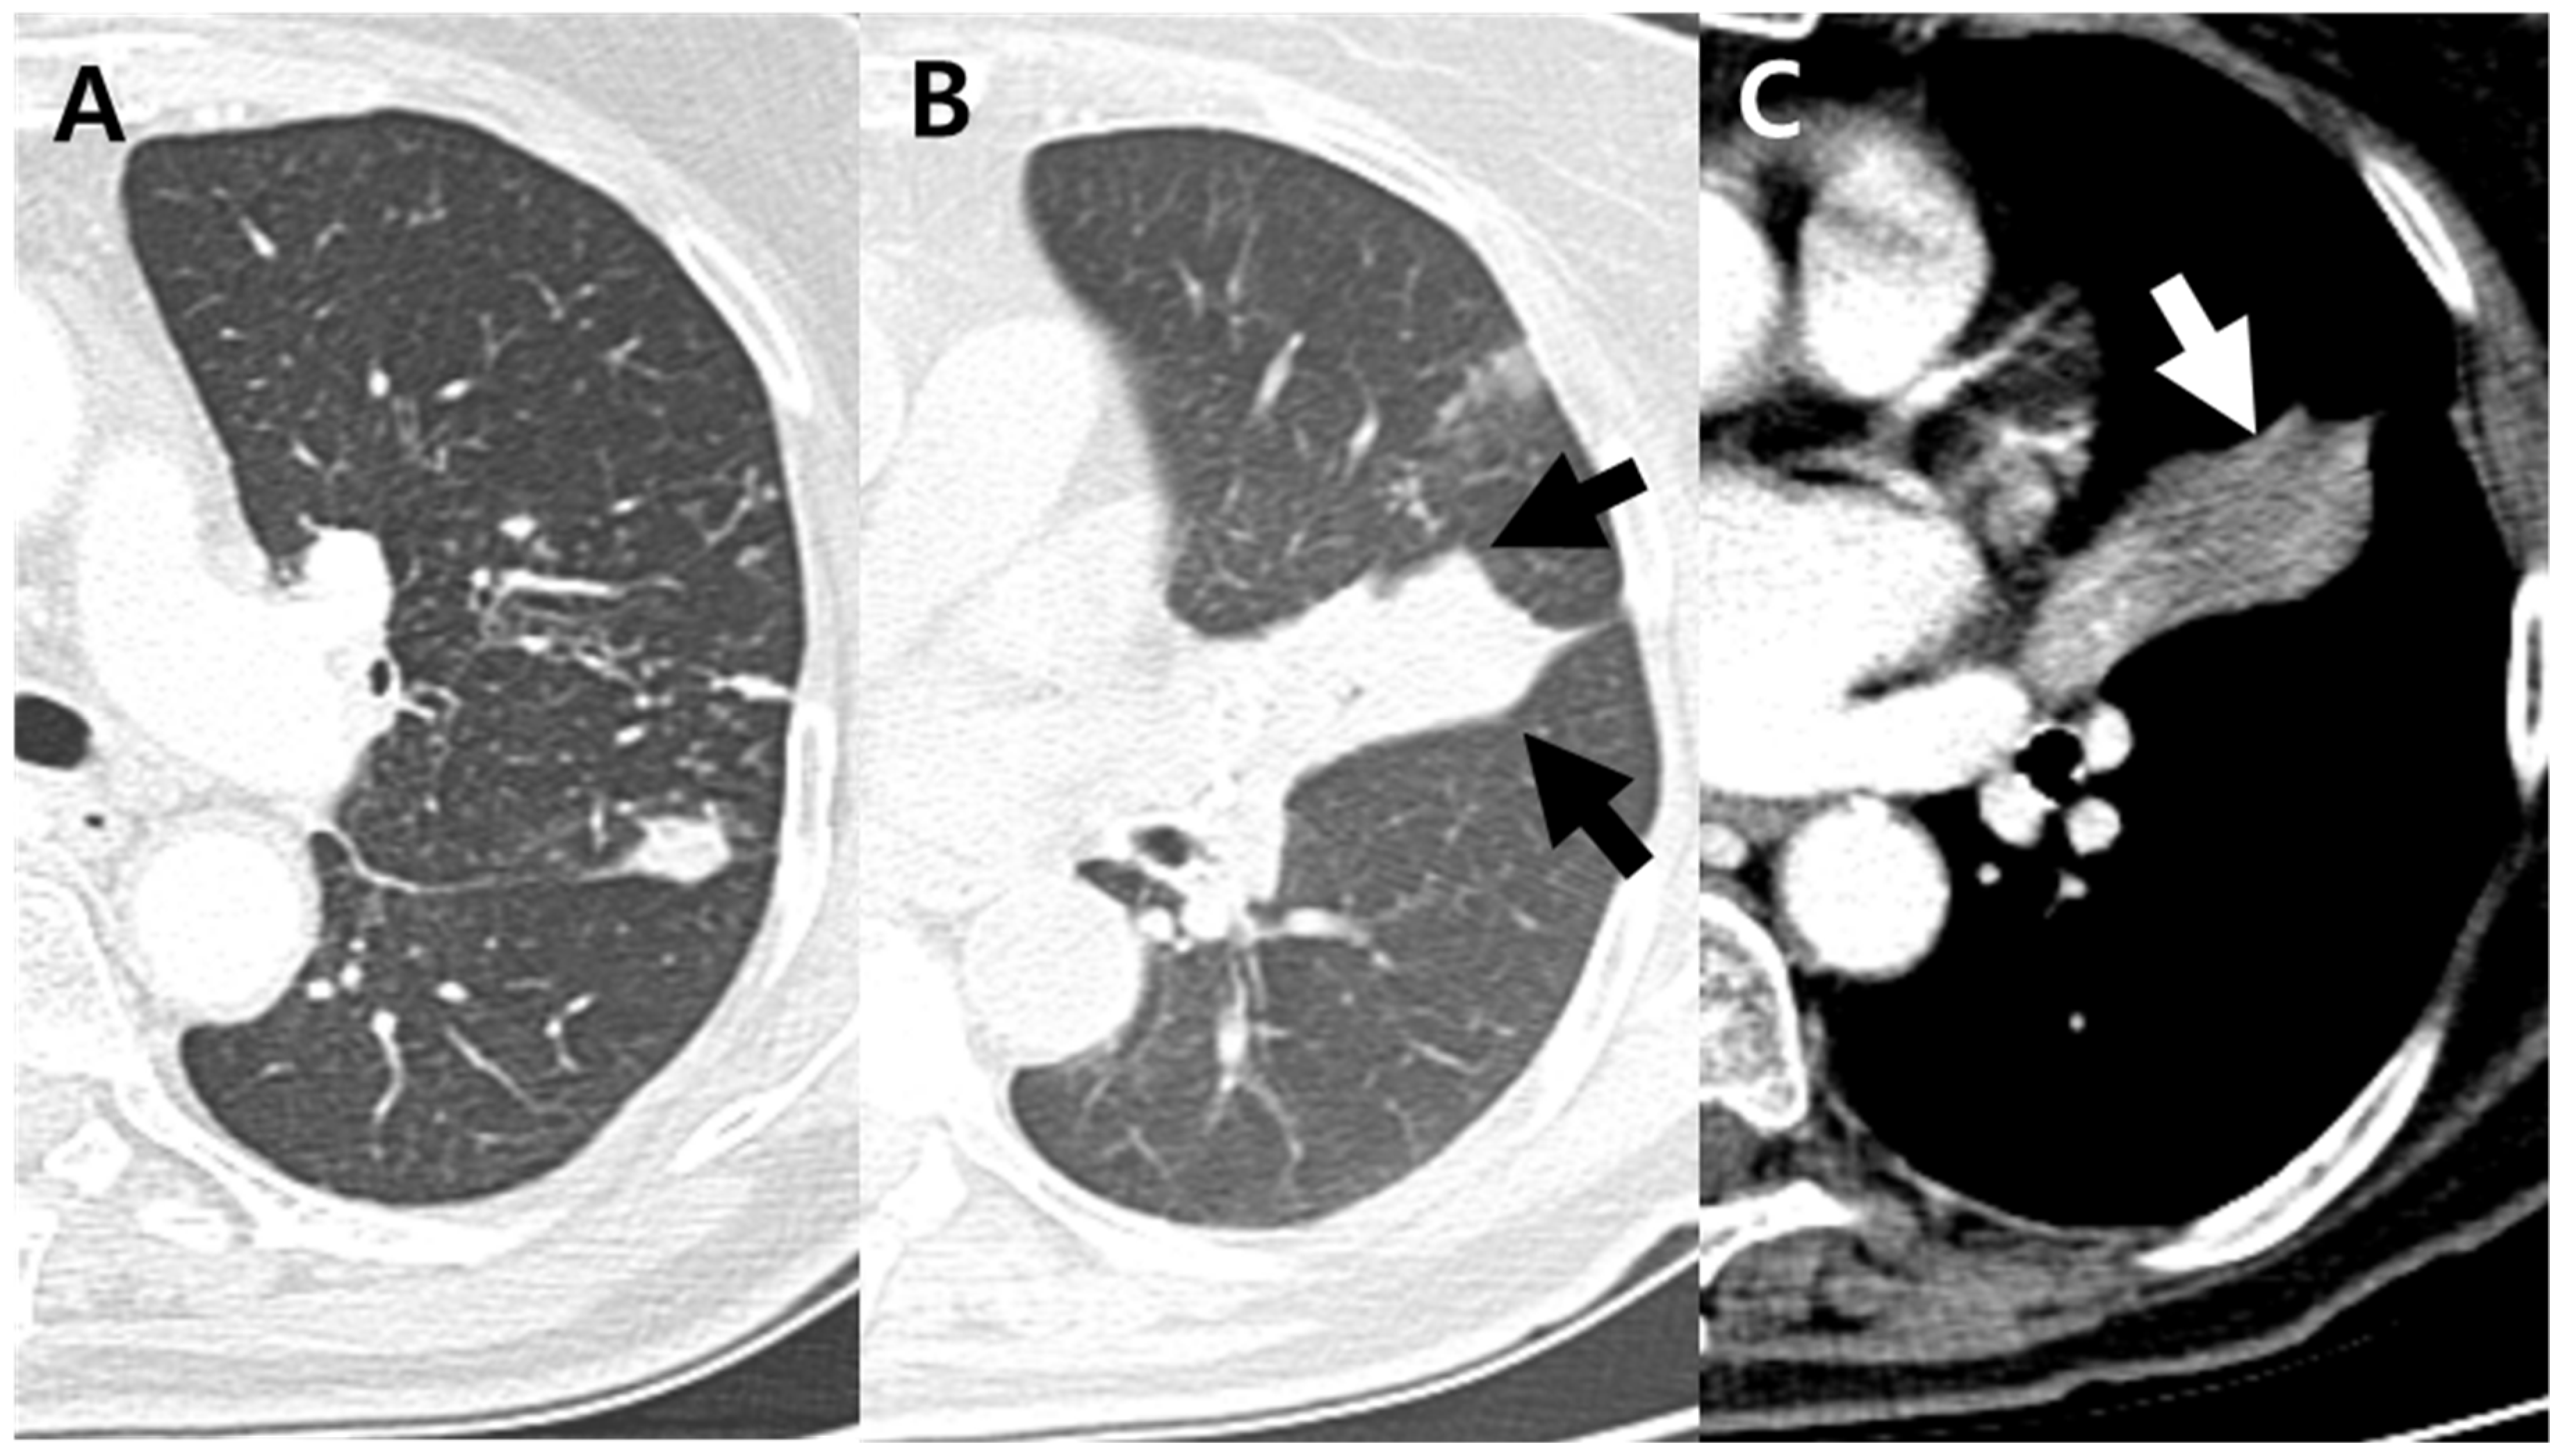

| Cavitation | 93 (46%) | 4 (14%) | 89 (51%) | 0.001 ** |

| Lymphadenopathy | 65 (32%) | 16 (57%) | 49 (28%) | 0.002 ** |

| Endobronchial involvement b | 39 (19%) | 13 (46%) | 26 (15%) | <0.001 *** |

| Upper lobe predominance | 150 (74%) | 9 (32%) | 141 (81%) | <0.001 *** |

| Lower lobe predominance | 27 (13%) | 12 (43%) | 15 (9%) | <0.001 *** |